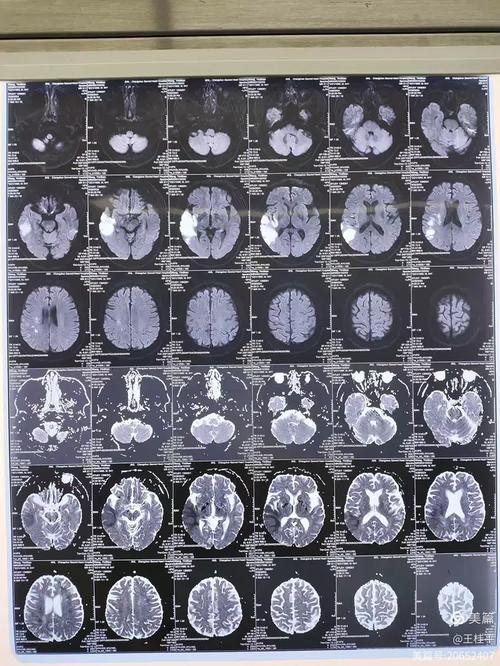

(图片来源网络,侵删) -

核磁(MRI):核磁共振是目前检查脑部病变最敏感、最准确的影像学方法之一,它能清晰地显示出非常早期的、微小的梗死灶,这些病灶可能在CT检查中完全看不出来。